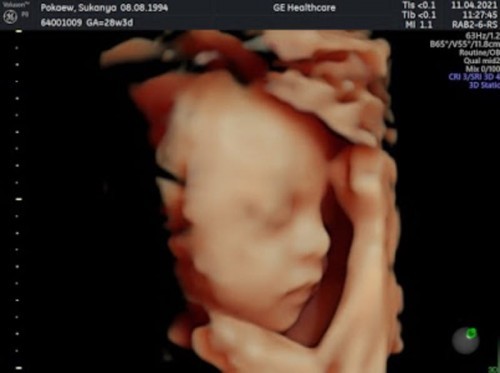

อัลตราซาวด์ 4 มิติค่ะ 28 week ป้าหมอชมว่าผมหล่อมากเลยครับ🥰 แม่ๆท่านไหน อัลตราซาวด์4 มิติบ้างคะ